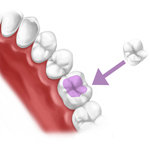

OTTURAZIONI ESTETICHE

Per otturazione si intende un restauro eseguito mediante stratificazioni successive di resina composita di colore simile al dente.

La scelta del metodo e dei materiali e' mirata alla protezione del dente a lungo termine e a far si' che l'otturazione si integri funzionalmente nella bocca in maniera invisibile.

Un tempo le otturazioni presentavano un colore argentato-metallico che, nel tempo, si ossidava assumendo un aspetto sempre piu' scuro.

Ora si utilizzano materiali senza mercurio e della stessa gradazione cromatica del dente naturale.

INTARSI IN COMPOSITO E IN PORCELLANA

Gli intarsi sono otturazioni eseguite in laboratorio, precedentemente preparata, usate per i denti posteriori (premolari e molari).

Sempre piu' pazienti desiderano sostituire le loro vecchie otturazioni d'amalgama con un materiale che sia biocompatibile e durevole nel tempo, in composito o in ceramica e che andra' a riempire la cavita' , ricostruendo la forma originaria.

Gli intarsi in ceramica rappresentano un'ottima scelta dal punto di vista funzionale ed estetico, perche' esteticamente molto validi, con elevata precisione nella chiusura marginale, un'ottima durata nel tempo e un'ottima biocompatibilita'. Negli intarsi in composito o in ceramica il colore viene scelto in base a quello del dente da restaurare e dei denti vicini, in modo da avere un effetto naturale.